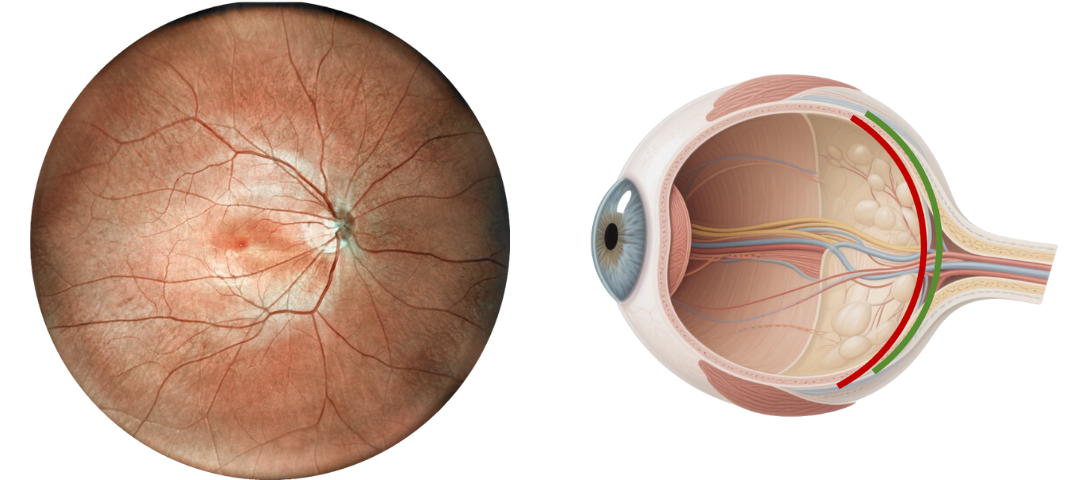

Optical Fundus Camera Get Retinal Layer

Traditional optical fundus cameras have a small field of view, generally 40 to 60 degrees, and can only see the retinal layer of the fundus, but cannot obtain a complete fundus image.

Scanning Laser Ophthalmoscope Obtain Retinal Layer and Choroidal Layer

Our scanning laser ophthalmoscope uses multi-wavelength laser scanning to penetrate the fundus, capture details of the retinal and choroidal layers, and obtain high-definition fundus images.